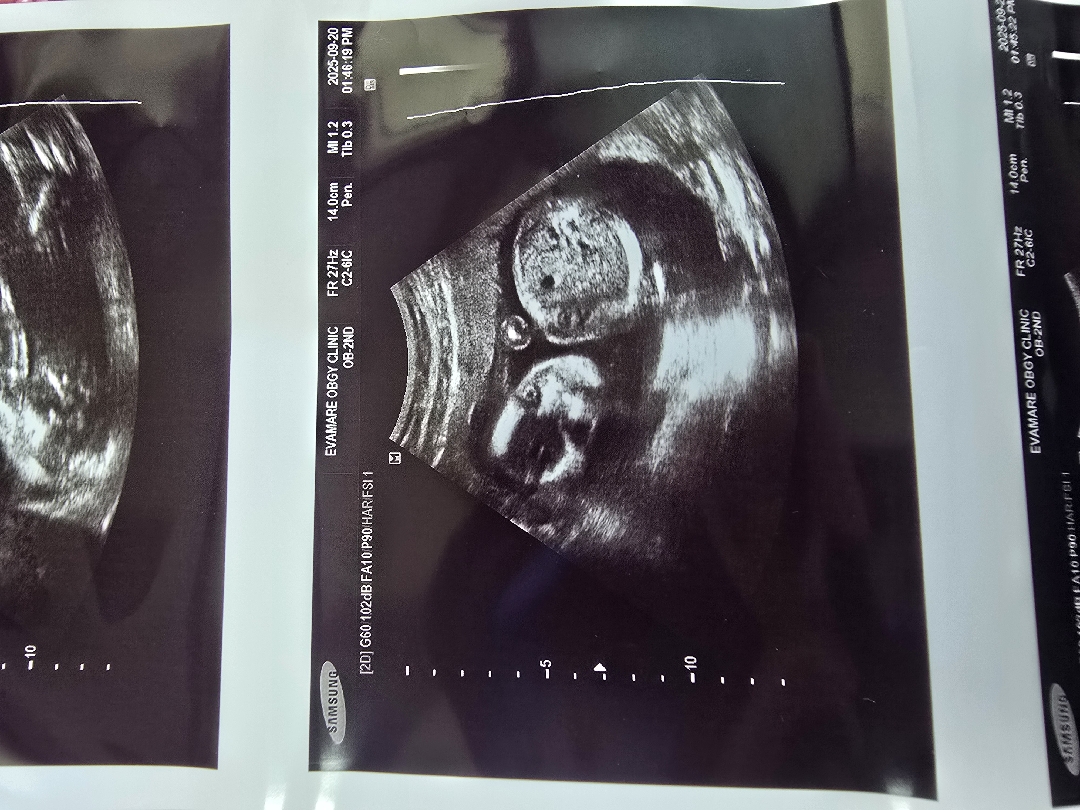

눈꺼풀이 아직 만들어지지 않아서 저리 보여요~ㅎㅎ

19주차 눈뜨나요??

눈이 뜬건지 모르겟어요 아시는분 알려쭈쎄용!!

의사쌤이 아직 눈 생성전이고 안구주변 뼈가 생기는거랬어요~